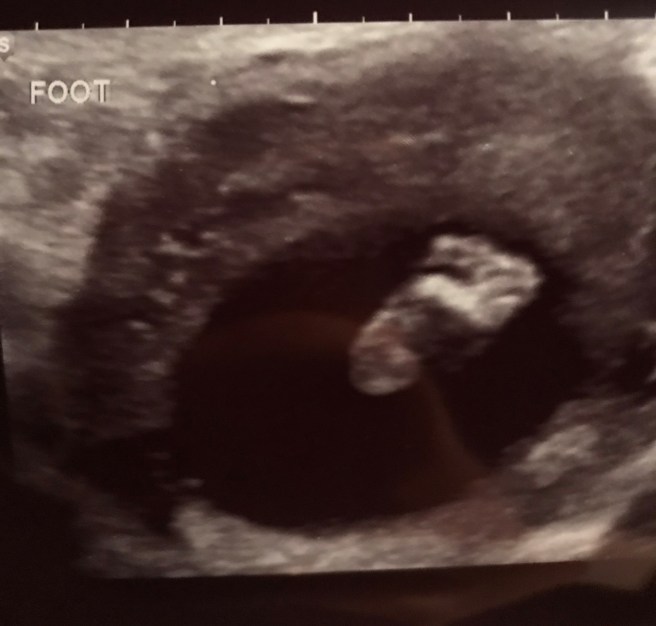

We were hooked up to an ultrasound machine and were able to see Evelynn!!! I don’t think I realized we would get to see her during the procedure. This is the first time Daddy was able to meet his little girl! To my surprise, she was alive. I was trying to guard my heart, waiting for some bad news or poor vital signs. Nope, not today. Thanks, Monday! I was basking in the glory of my sweet sweet gummy bear who had GROWN since our first ultrasound and she was so active. I was confused. Why is she so full of life when she’s not compatible for it?! I pushed those negative thoughts aside and just thanked God over and over in my head for that confirmation of life. I was asked again about my options and if I had made a decision. I quickly denied any need for those options. No matter what the test result was, we we’re on this journey for as long as God would allow us to be. The feeling of buckling up before the roller coaster. I had no idea what was in store, but I wanted God to use me. “Our journey will end when You say so and not a moment before.”

Little gummy Evelyn was trying to hold on so she could teach all of us.